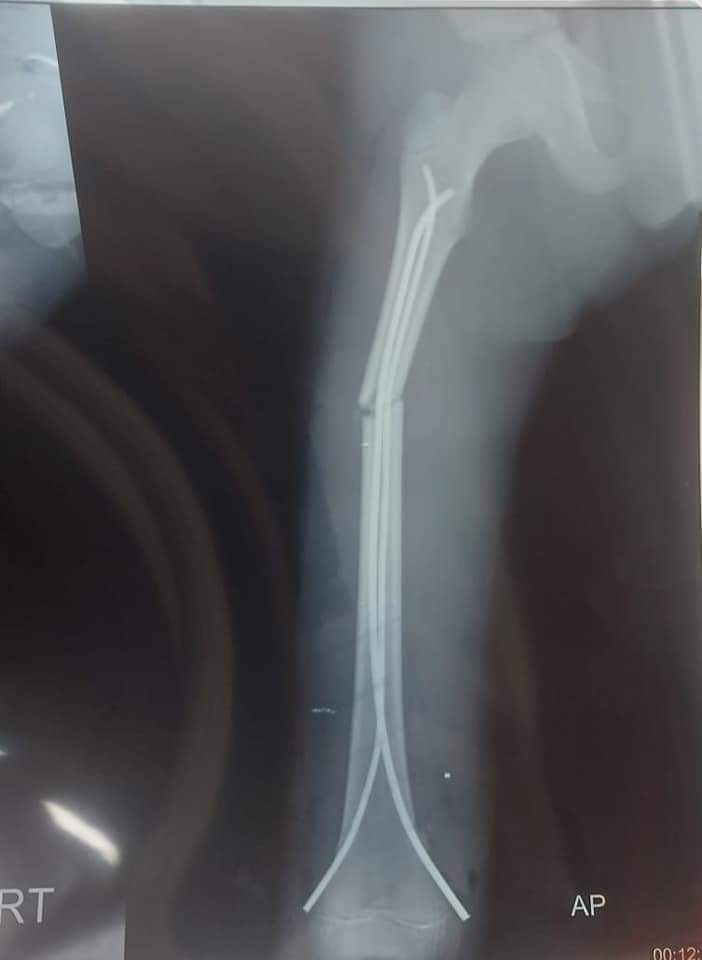

وأضاف مدير المستشفى، في بيان له، أن أطباء قسم جراحة العظام أجروا عملية تثبيت لكسر عظمة الفخذ للطفل باستخدام أسلاك معدنية مرنة، وتمت الجراحة بنجاح، كما تم حجز المريض بالقسم الداخلي للملاحظة، ثم تعافى المريض وخرج من المستشفى بعد استقرار حالته الصحية تماما.